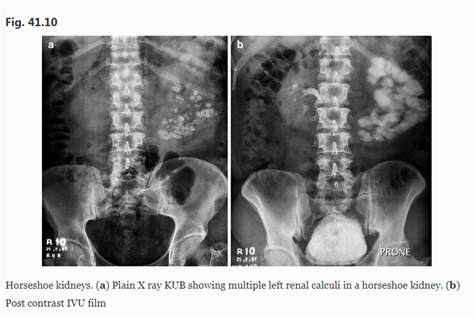

尿石症是马蹄肾最常见的并发症,据报道发生率为 21-60%,PCNL 被公认为在这些病例中既安全又有效。63尽管如此,就像在盆腔异位肾脏和其他旋转不良的肾脏中一样,可能存在对马蹄肾中与 PCNL 相关的邻近结构的不可接近性和损伤的恐惧。因此,就 PCNL 而言,值得注意的是马蹄肾解剖结构优于正常肾脏的一个优势。在肾解剖结构正常的患者中,在 PCNL 期间进入上极肾盏通常需要经肋上入路,具有相关的胸膜损伤风险。相比之下,马蹄肾中的上极通路相对安全,因为肾脏远离胸膜的移位较小,并且报告的相关气胸发生率较低。64 , 65此外,上极入路有助于清除结石,因为肾镜与肾脏长轴对齐有助于将范围操纵到上肾盏、肾盂、下肾盏、肾盂输尿管连接处 (PUJ) 和近端输尿管。

另外两个因素使 PCNL 成为治疗马蹄肾内结石的有吸引力的选择。这些患者通常有非常显着的结石负担,这使得 PCNL 成为一种有效的结石清除技术,所需的手术次数最少(图41.10a 和 b)。此外,插入肾盂的输尿管往往会向上和横向移位,限制了体外冲击波碎石术后结石碎片通过的机会。

马蹄肾。( a ) X 线平片 KUB 显示马蹄肾中有多个左肾结石。( b ) 后对比 IVU 胶片